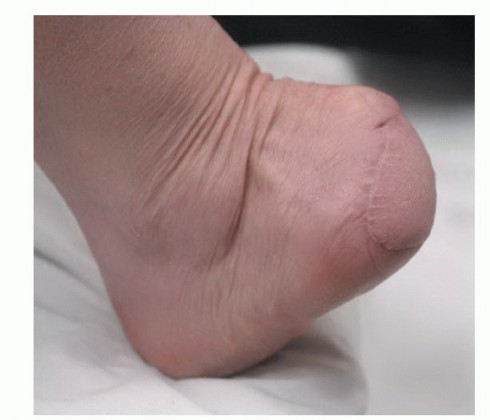

- كتلة أو تورم غير مبرر: ظهور كتلة جديدة أو تورم في أي جزء من القدم أو الكاحل، سواء كانت مؤلمة أم لا. قد تكون هذه الكتلة صلبة أو ناعمة، ثابتة أو متحركة.

- ظهور شامة جديدة أو تغير في شامة موجودة (عدم انتظام الحواف، تغير اللون، زيادة الحجم، حكة أو نزيف) – قد يشير إلى الورم الميلانيني.

- تغير في شكل القدم أو الأصابع: تشوهات ملحوظة في بنية القدم.